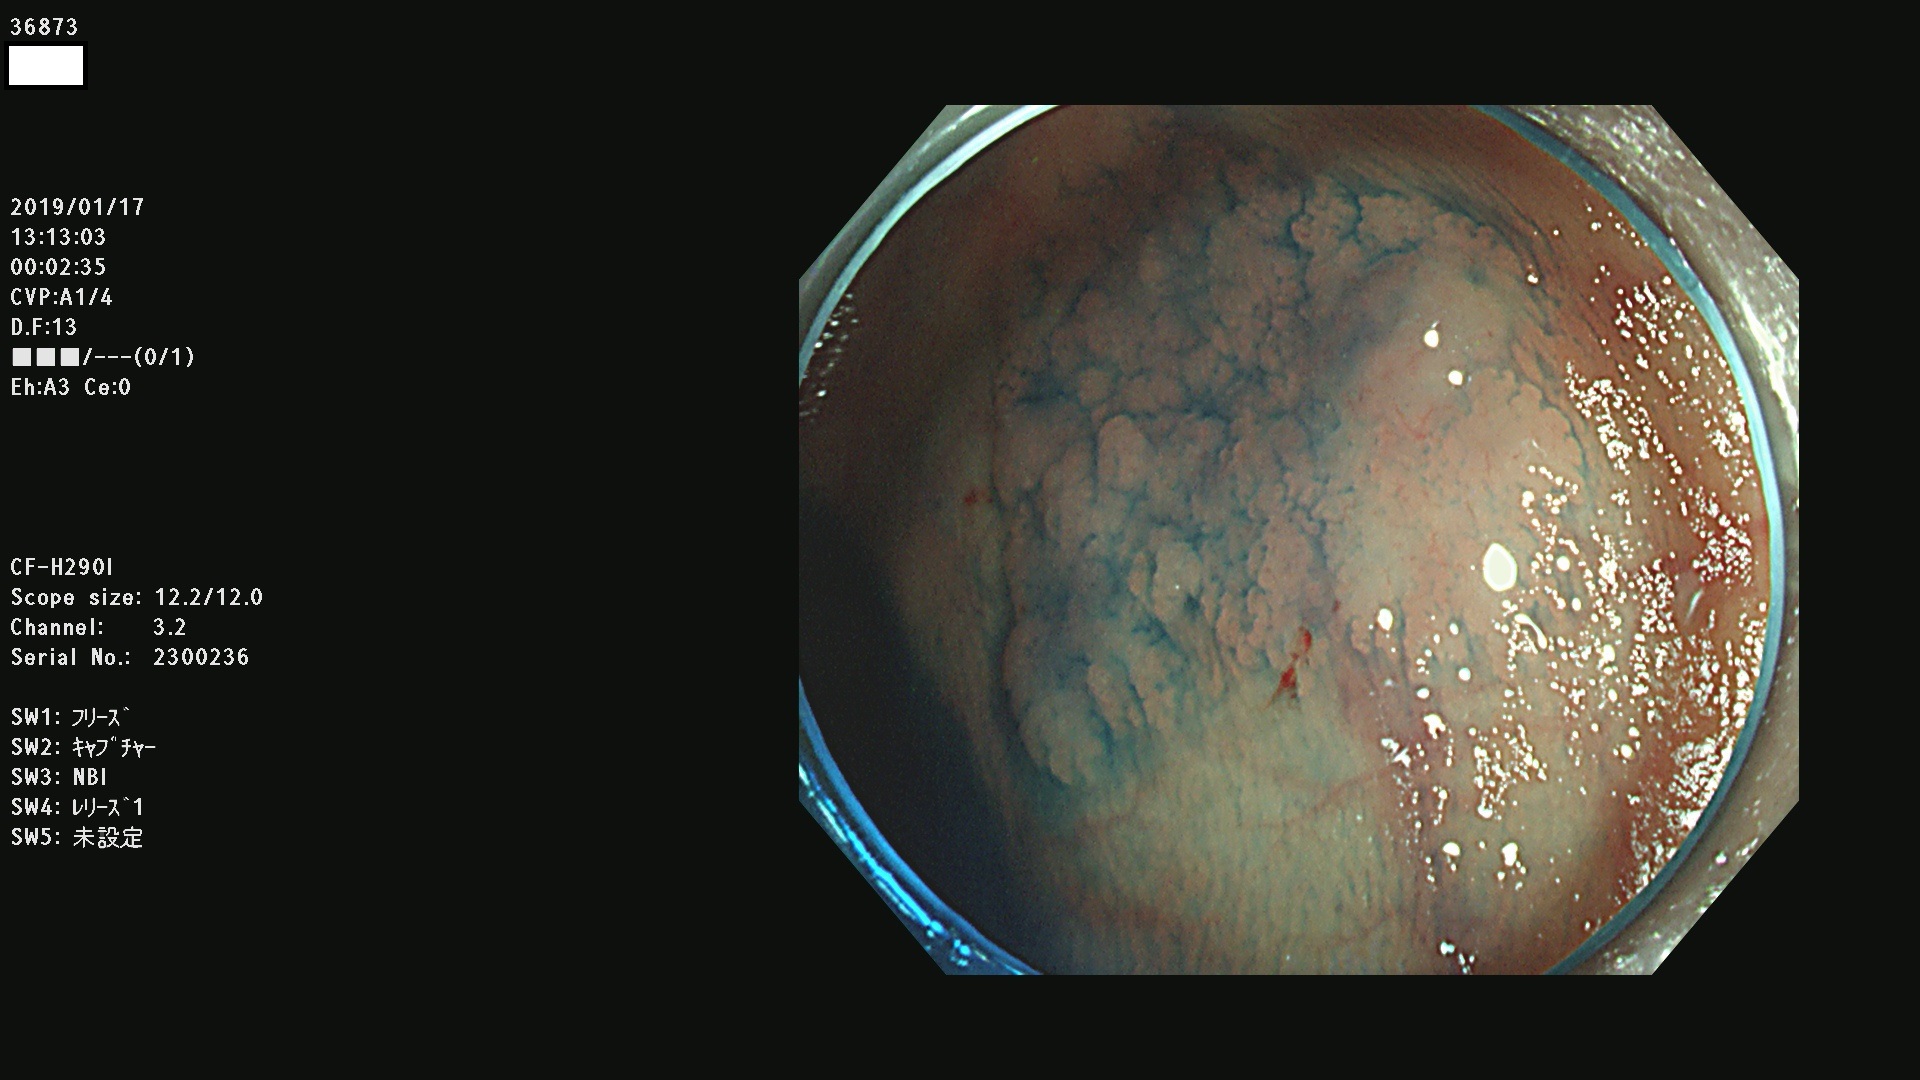

36804 36806 36807 36808 36809 36810 36811 36813 36815 36816 36817 36818 36820 36821 36822 36824 36825 36826 36828 36829 36830 36831 36832 36833 36834 36835 36837 36840 36841 36842 36845 36846 36848 36849 36851 36852 36853 36854 36855 36857 36859 36860 36861 36862(SSAPのみ) 36863 36864 36866 36868 36869 36870 36873 36875 36877 36878 36879 36881 36882 36883 36884 36885 36886 36887 36888 36889 36891 36892 36893 36894 36895 36896 36897 36898 36899

発見困難で危険性の高い平坦型病変(上記100名より抽出)